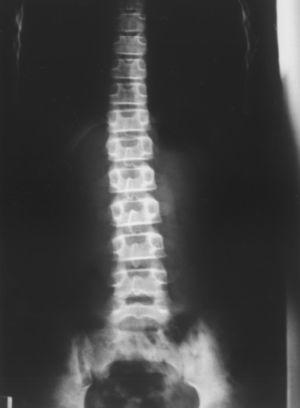

Radiografía simple de columna (en bipedestación y descalza). Ligera escoliosis lateral dorsolumbar de convexidad derecha.

Figura 3. Radiografía de columna simple (en bipedestación y con pies descalzos): donde se aprecia ligera escoliosis lateral dorsolumbar de convexidad derecha.